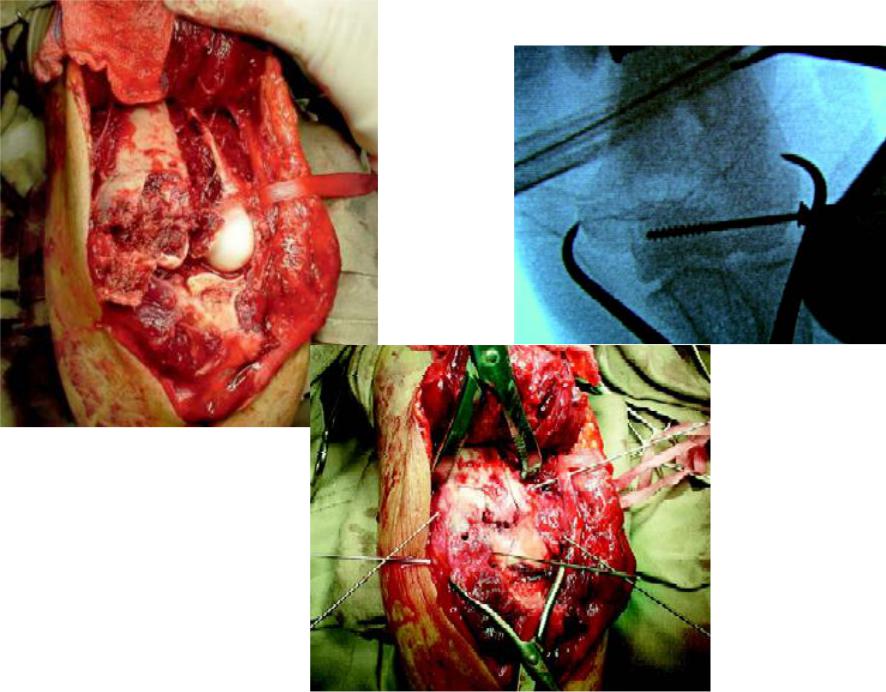

Доступ

Доступ – заднемедиальный

параолекрановый

Клинический пример 3